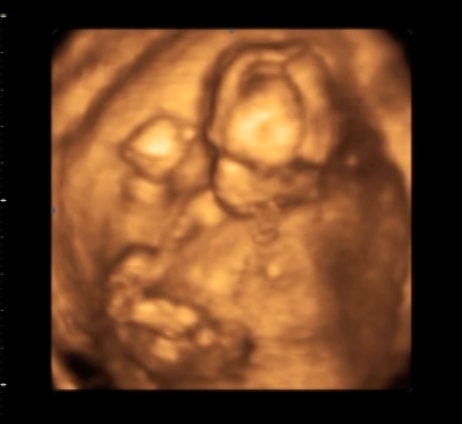

16 weeks and 2 days

This was the non-medical ultrasound. It lasted about 15 minutes and we got the entire "movie" on dvd, so we have tons of pictures, both in 2D and 3D. I made these pictures a bit smaller than usual because I think some of the detail is lost when I enlarge the photos.

| Tiny hands and feet. |

| Open mouth. :) |